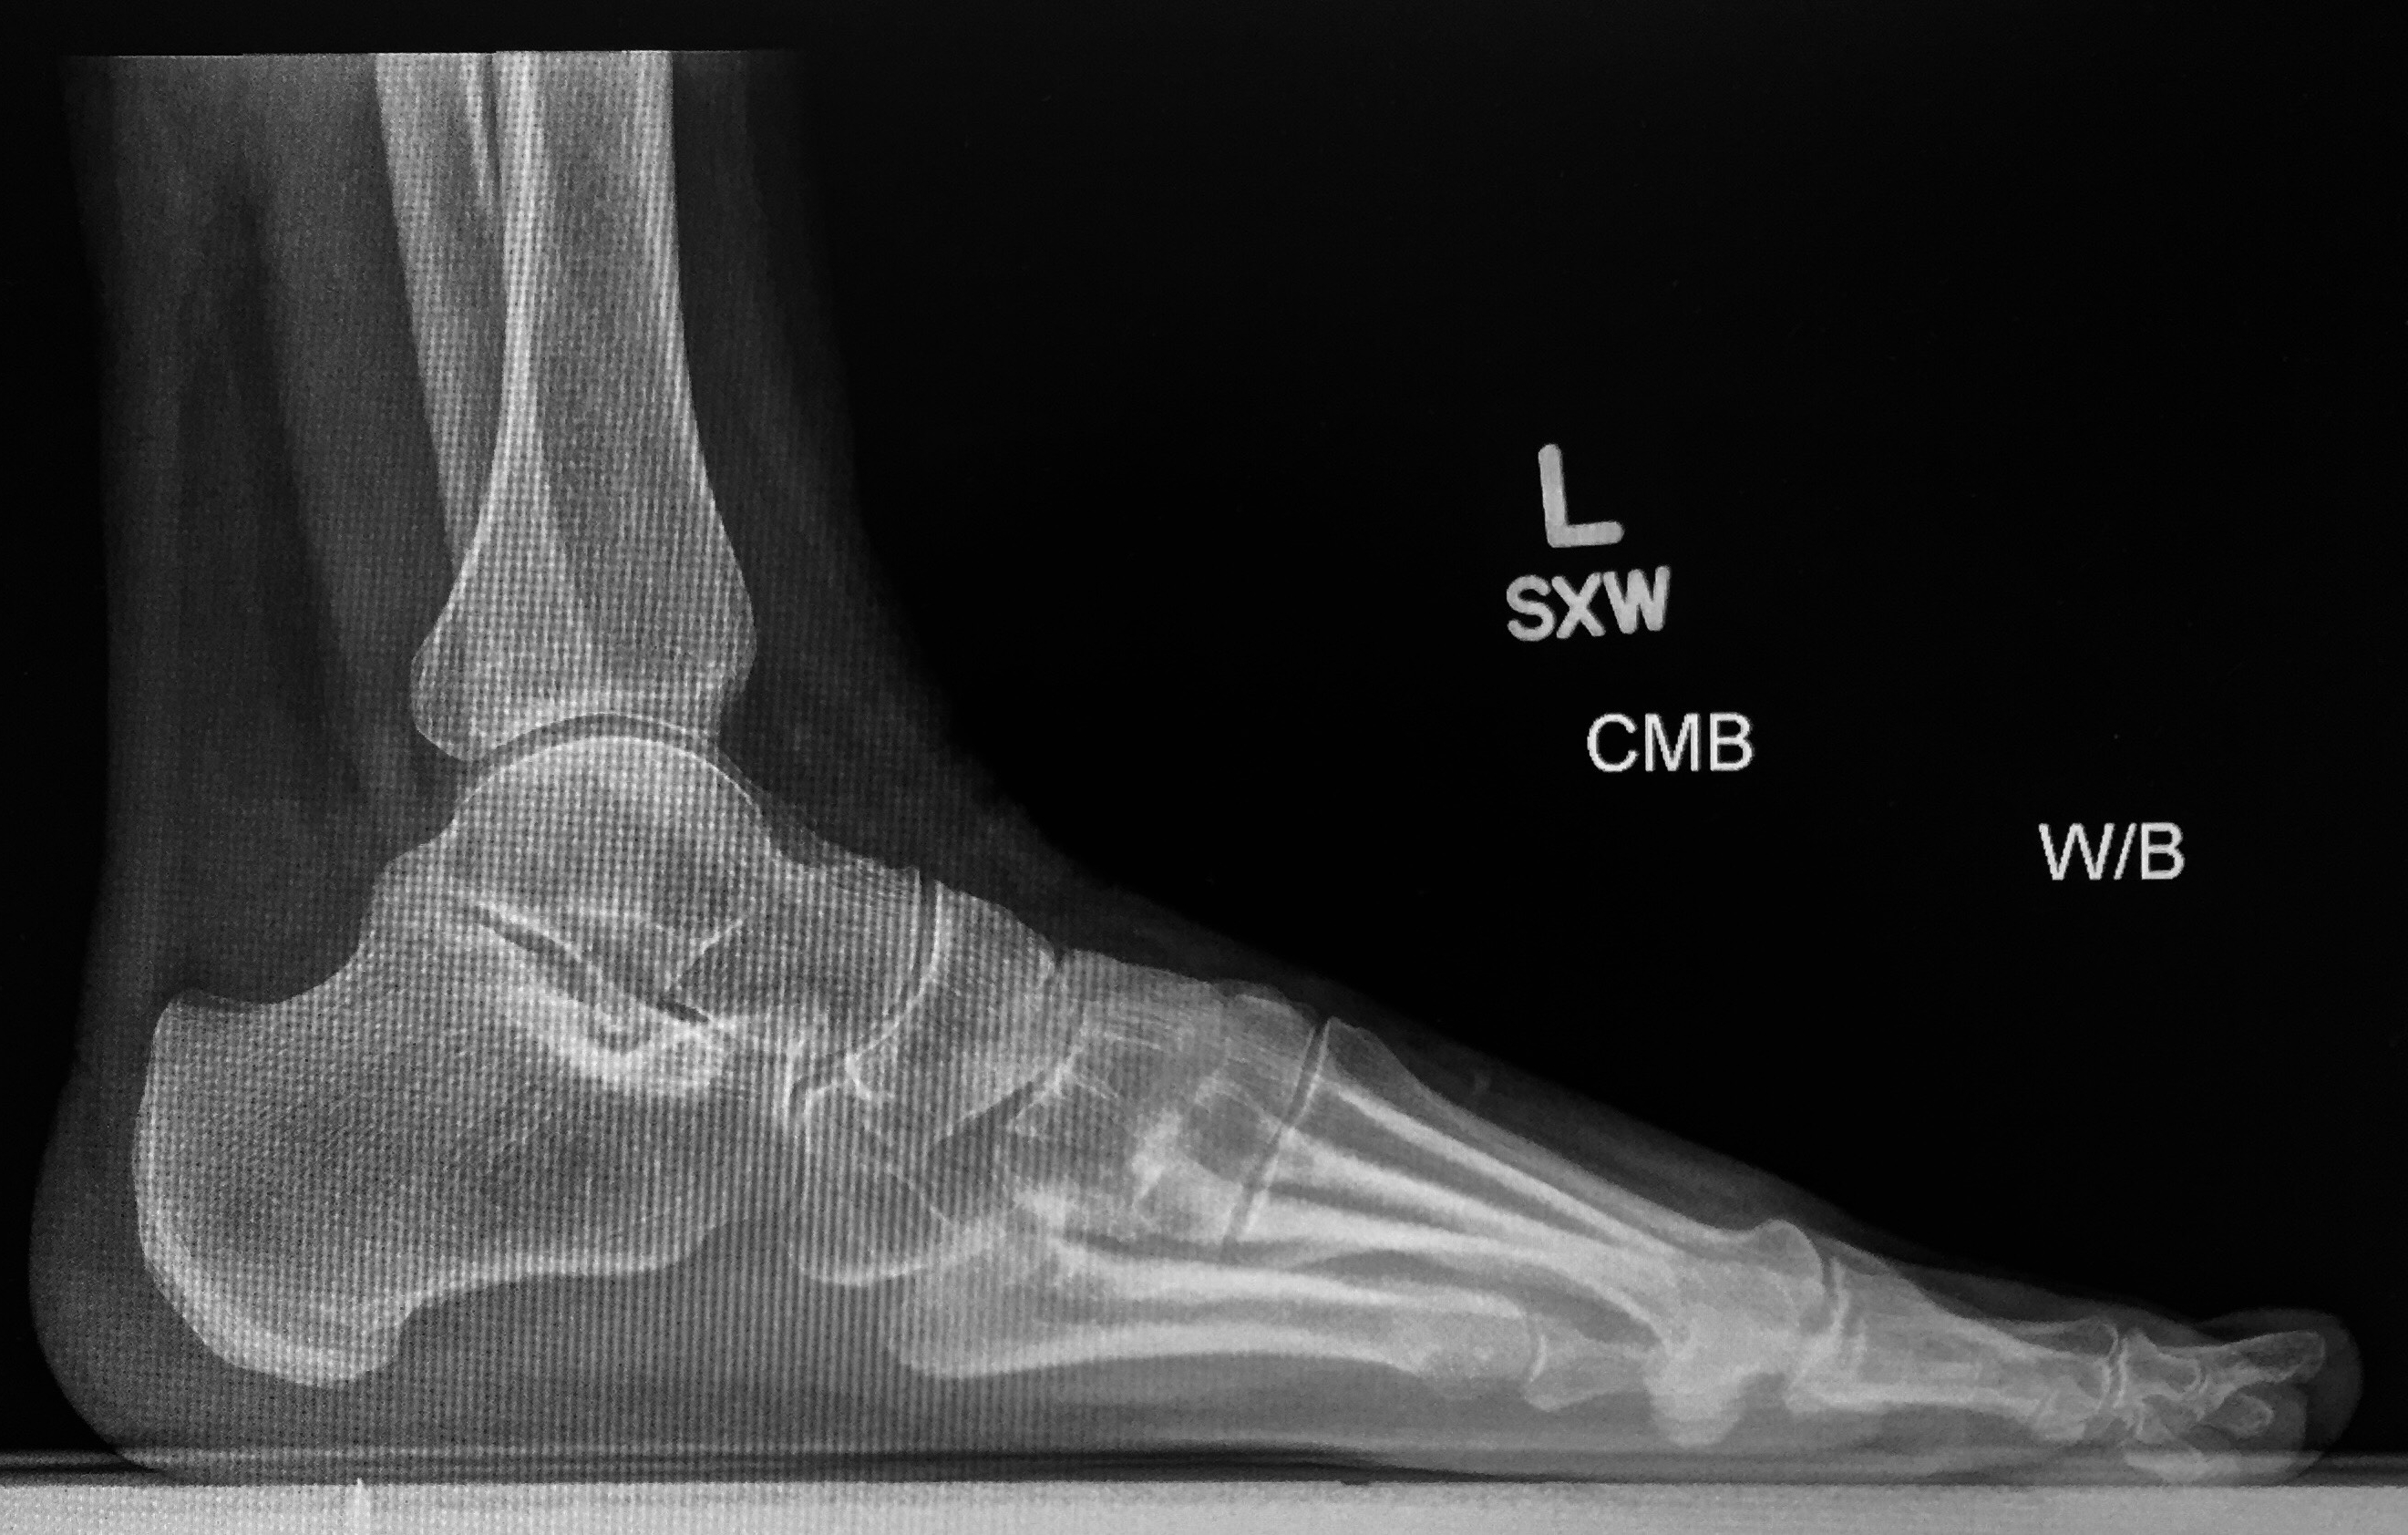

This is a Lateral view of a painful heel, Left foot.